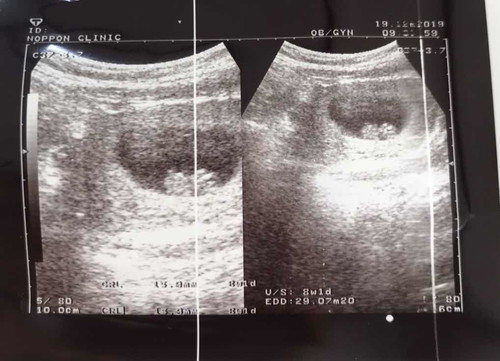

8 week 1 day ??

กำหนดคลอด 29 กรกฎาคม 2563 จ้า ?? น้องสร้างเเขน ขา หัวใจเต้น ดีใจมากเลยค่ะ ?